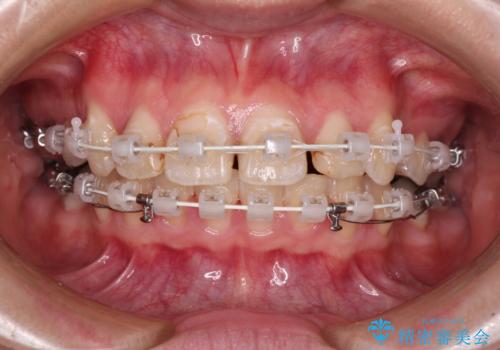

- 審美装置

- 2年7ヶ月

- 10-30回

下顎は過剰歯が埋伏しており、それが原因となってスペースが閉じなかったため、途中で抜歯して速やかに仕上げました。